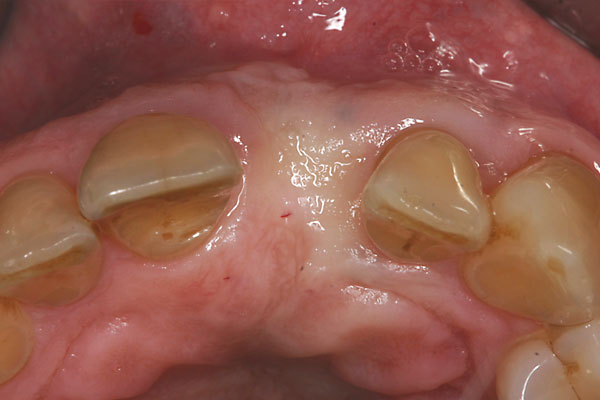

Fall: Von der Prothese zur fixen Krone